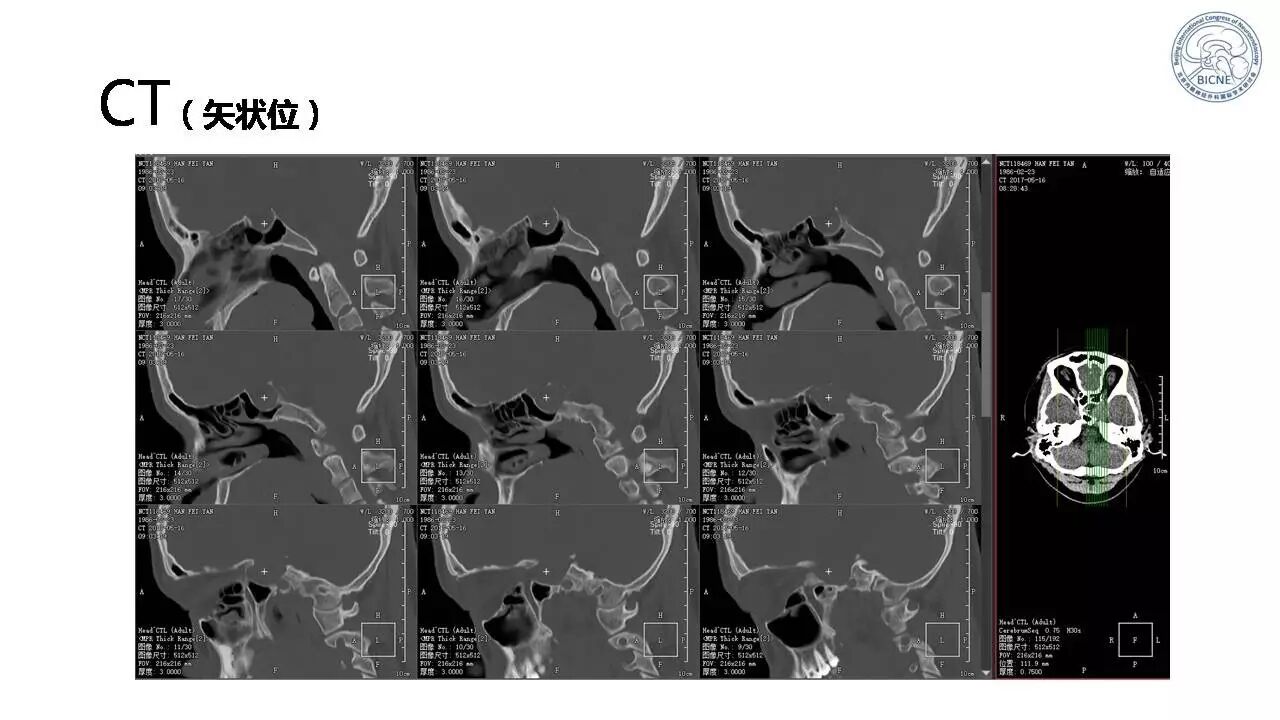

(四)张亚卓教授:复发脊索瘤经鼻内镜治疗

![]()